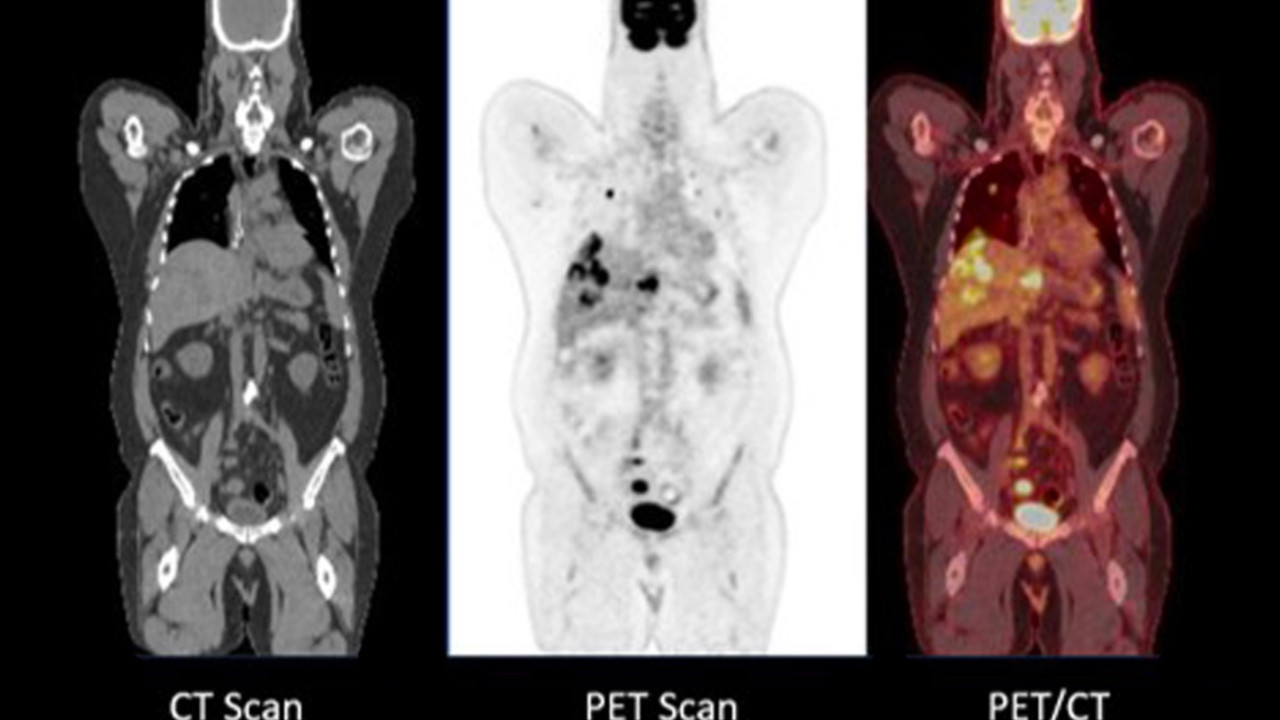

Fakat uzmanlar, bu tür ilaçların PET-BT taramalarını engellediği ve bu sebeple doktorların kanser ve diğer rahatsızlıkları tespit edemediğini açıkladı. Bunun sebebi olarak da vücuttaki GLP-1 oranının kanser ve benzeri rahatsızlıkların görülmesini engellemesi gösterildi.

PET-BT taramaları, doktorlara vücutta neler olup bittiğine dair ayrıntılı bir tablo sunmak için iki güçlü görüntüleme aracını bir araya getiren sistem olarak bilinirken PET taramasında kan dolaşımına karışan ve dokular tarafından emilen radyoaktif bir madde kullanılır.